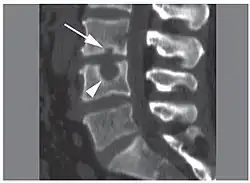

CT scan in the sagittal plane of two Schmorl's nodes. The small Schmorl's node at the inferior endplate of the L3 vertebral body (arrow) has typical features, being broad-based at the endplate, with well-defined contours and thin marginal sclerosis. A large and less typical Schmorl's node (arrowhead) is observed at the superior endplate of L4.[3]

Schmorl's nodes can be detected with X-rays, although they can be imaged better by CT or MRI. They are considered to be vertical disc herniations through the cartilaginous vertebral body endplates. Schmorl's nodes can sometimes be seen radiographically, however they are more often seen on MRI, even when not visible on plain X-rays. They may or may not be symptomatic, and their etiological significance for back pain is controversial. In a study in Spine by Hamanishi, et al., Schmorl's nodes were observed on MRI in 19% of 400 patients with back pain, and in only 9% of an asymptomatic control group. The authors concluded that Schmorl's nodes are areas of "vertical disc herniation" through areas of weakness in the endplate.[4]